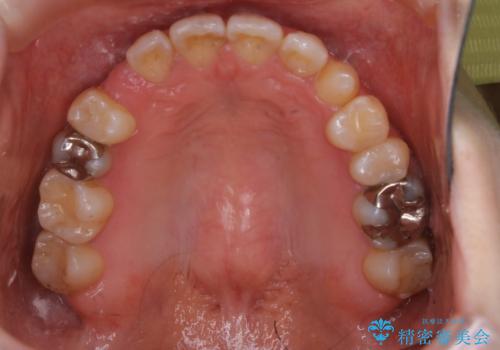

- 受け口で、前歯の嚙み合わせが気になるとの事でご相談にいらした方です。先天的に右上犬歯がなく、左上犬歯も小さい状態でした。矯正治療にて周囲の歯を動かして歯のスペースを確保した上で、被せものにて歯を作っていきました。

歯科技工士さんの熟練した技術により、周囲の歯としっかりなじむ天然歯のような被せ物をお作りすることが出来ました。

矯正治療と補綴治療をうまく組み合わせることで、美しい口元に仕上げることが出来ました。矯正治療、補綴治療をまとめて行える総合歯科治療を体現した治療といえます。